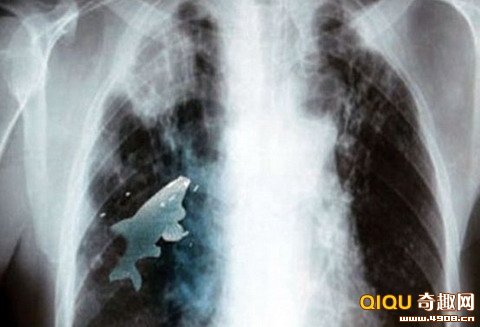

2012年5月,印度一名12岁男孩在一条河中玩耍时呛水,不慎将一条小金鱼吸入肺中。医生迅速为他进行手术,取出了这条“肇事小鱼”。医生表示,在他们用支气管镜检查时发现,巴瑞拉肺中的小鱼依然活着。